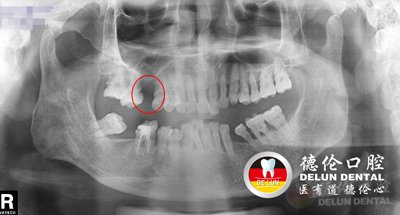

梁先生术前牙齿X光片,上颌下颌均有缺牙

程武主任表示,患者梁先生的缺牙不是一朝一夕的事情,大家可以看梁先生的牙片,下颌由于缺牙多年,相邻两侧的牙齿失去了支持,会在咀嚼力的作用下向缺隙处移位倾倒,出现间隙,容易导致塞牙、咬合系统紊乱等。

梁先生术后牙齿X光片